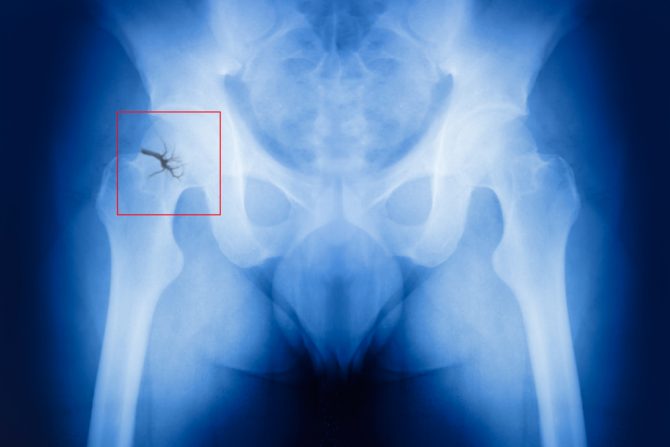

Među 26.318 žena, koje su u vreme kada su odabarane za studiju bile u dobi od 35 do 69 godina, 822 slučaja preloma kuka su primećena tokom 20 godina studija - što je predstavljalo nešto više od 3 odsto populacije posmatranog uzorka. Nakon prilagođavanja faktorima kao što su pušenje i godine starosti, vegetarijanke su bile jedina grupa sa povećanim rizikom od preloma kuka. Ova studija je jedna od retkih koja upoređuje rizik od preloma kuka kod vegetarijanaca i mesojeda gde je pojava preloma kuka potvrđena na osnovu bolničke dokumentacije. Naučnici naglašavaju da postoji potreba za dodatnim istraživanjem tačnih uzroka zašto su vegetarijanke u većem riziku od preloma kuka.

Kako indeks telesne mase utiče na prelom kuka

Istraživački tim je otkrio da je prosečan indeks telesne mase BMI među vegetarijankama  bio nešto niži od proseka među ostalim ispitanicama. Prethodna istraživanja, kako podsećaju, pokazala su vezu između niskog BMI i visokog rizika od preloma kuka. Niži BMI može da ukaže na manju težinu, što može da znači lošije zdravlje kostiju i mišića i veći rizik od preloma kuka. Potrebno je dalje istraživanje kako bi se utvrdilo da li je nizak BMI razlog za uočeni veći rizik kod vegetarijanki.